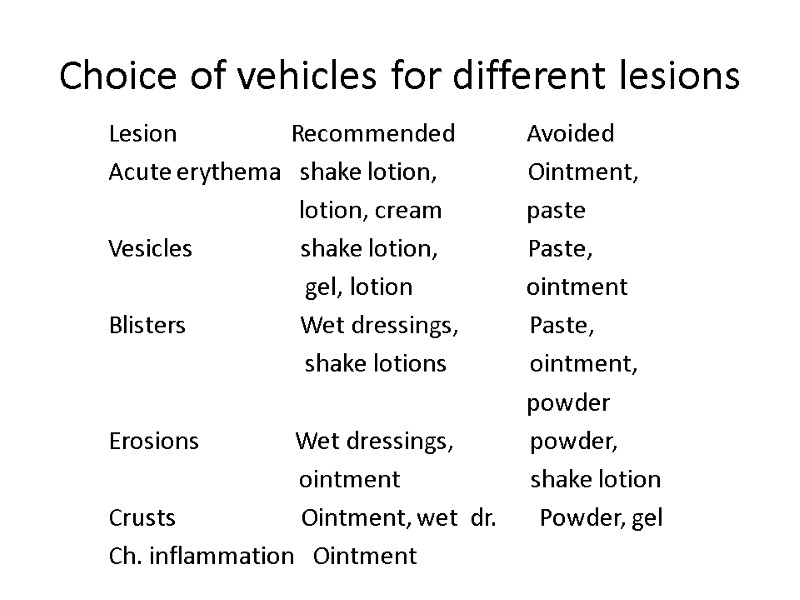

Choice of vehicles for different lesions Lesion Recommended Avoided Acute erythema shake lotion, Ointment, lotion, cream paste Vesicles shake lotion, Paste, gel, lotion ointment Blisters Wet dressings, Paste, shake lotions ointment, powder Erosions Wet dressings, powder, ointment shake lotion Crusts Ointment, wet dr. Powder, gel Ch. inflammation Ointment